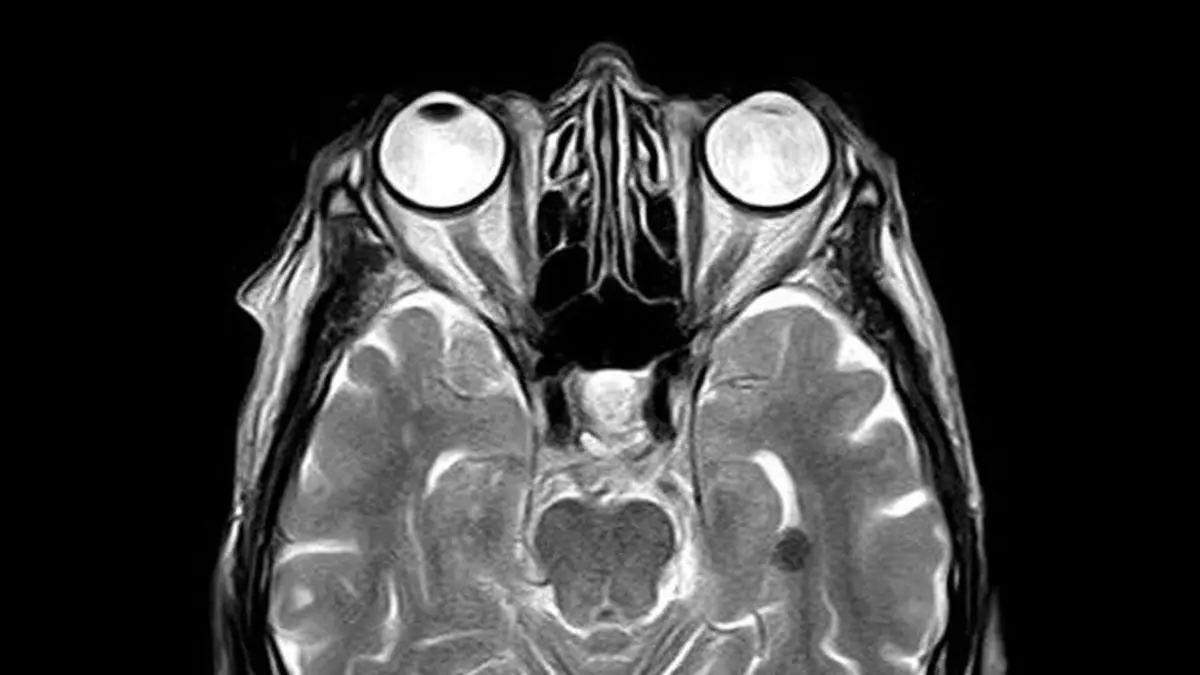

تحقیقات جدید محققان دانشکده پزشکی "دانشگاه ویرجینیا" نشان می‌دهد، حتی ضربه‌های مغزی خفیف باعث اختلال شدید و طولانی مدت در مغز می‌شود و مدت زمان زیادی طول می‌کشد تا مغز سموم خود را پاکسازی کند که این موضوع می‌تواند سبب ایجاد بیماری‌هایی مانند آلزایمر، زوال عقل و سایر بیماری‌های تحلیل برنده عصبی شود.

تحقیقات محققان طی این مطالعه نشان داد که ضربات مغزی می‌تواند اثرات طولانی مدت داشته باشد. وقتی مغز متورم می‌شود، به جمجمه فشار می‌آورد و در این بین، رگ‌های کوچک لنفاوی که مغز را پاکسازی می‌کنند، به دام می‌افتند. به گفته محققان، این فشار بر عروق باعث اختلال جدی و طولانی مدت در توانایی مغز در پاکسازی خود از سموم می‌شود. دانشمندان با آزمایش بر روی موش‌های آزمایشگاهی دریافتند که این اختلال می‌تواند حداقل دو هفته و احتمالاً بسیار بیشتر طول بکشد.

فناوری‌های تصویربرداری نوظهور ممکن است در نهایت امکان شناسایی افرادی را که ممکن است بیشترین پیامدهای ضربه مغزی را تجربه کنند، برای پزشکان فراهم کند.